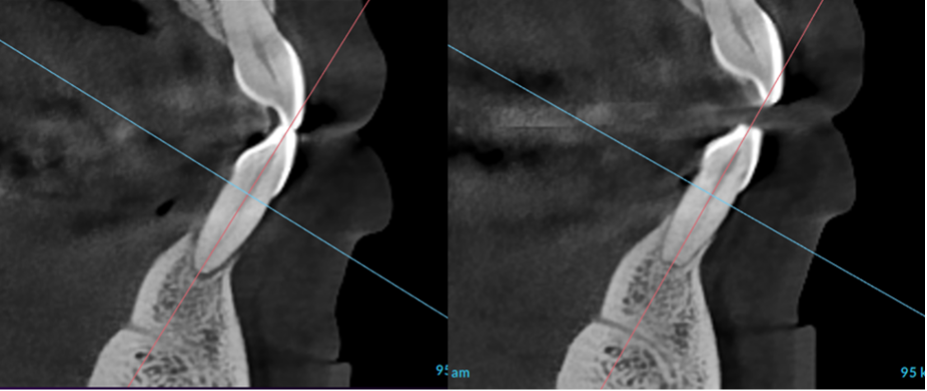

Radiographs showed severe bone loss. At first glance, this looked like a tooth destined for extraction.

Next came periodontal endoscopy, allowing us to go beneath the gumline and ensure the root surfaces were truly clean.

Weeks later, pocket depths had dramatically improved—nearly all were resolved.

The Proof Is in the Bone

Look at tooth #24. Bone regenerated.